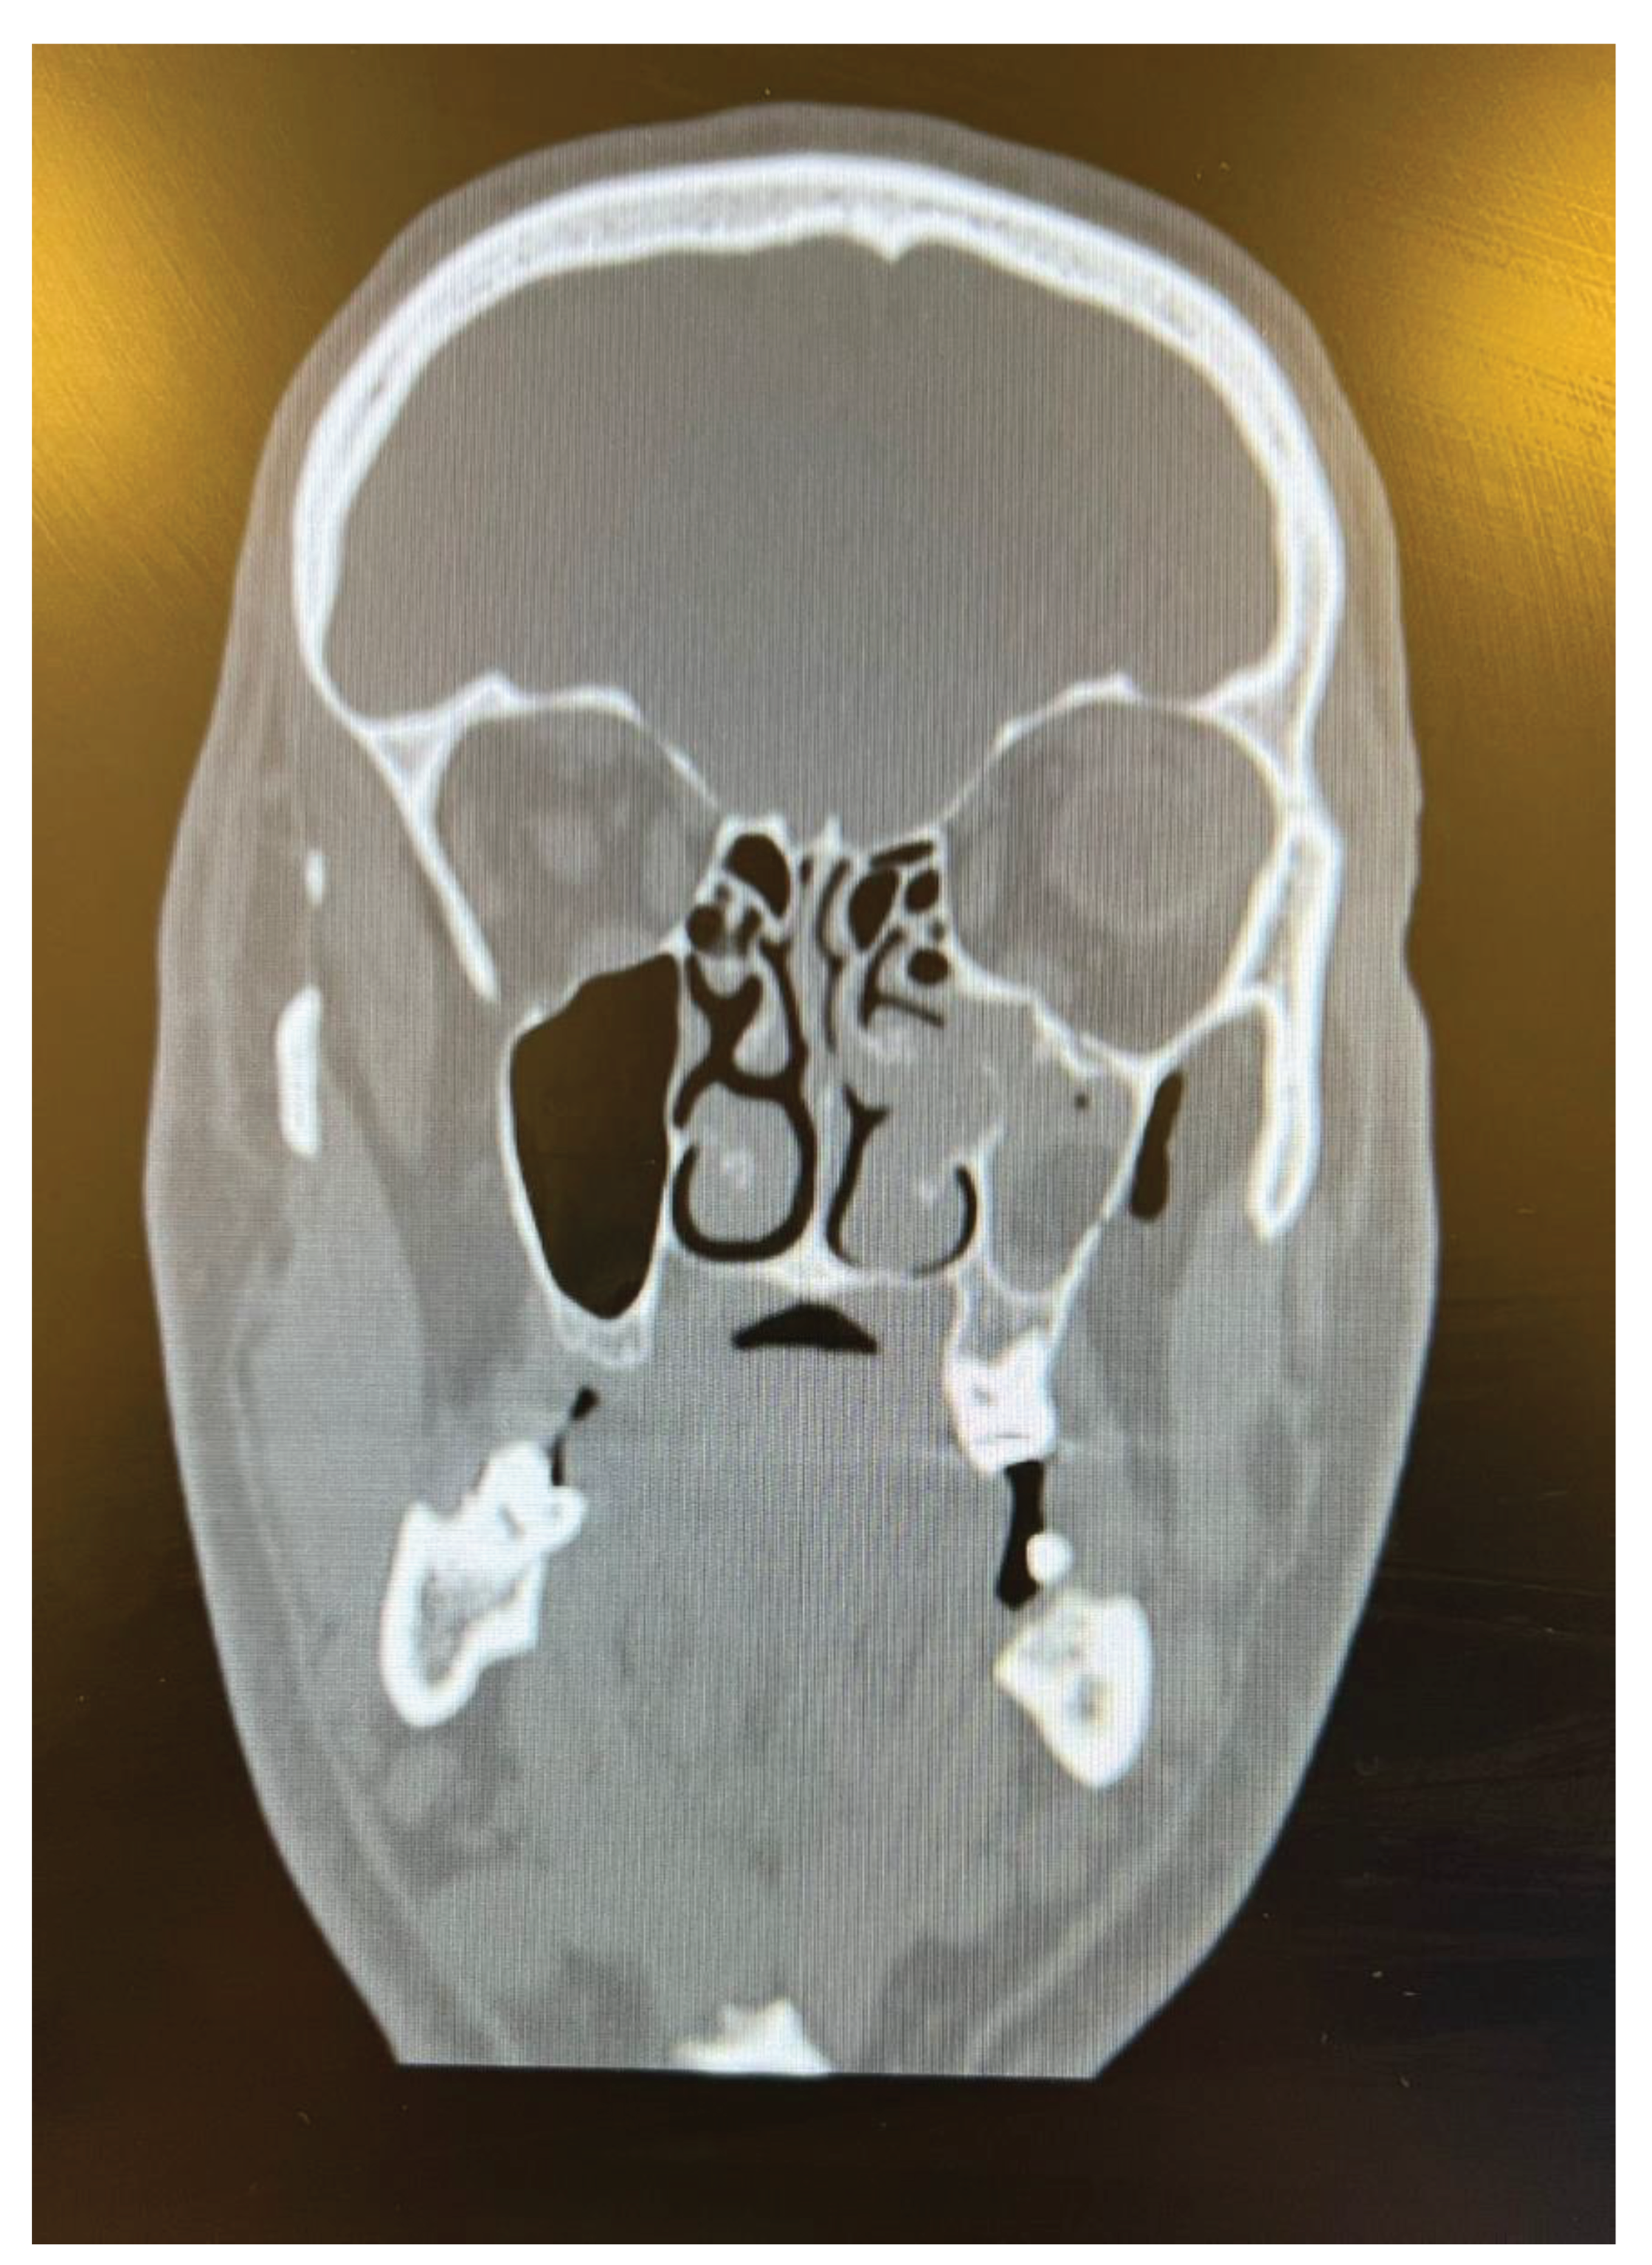

As plastic surgeons, we observed that there were not only hand injuries, but also maxillofacial traumas other than cuts in other body parts. During the Eid al-Adha period, the number of people traveling between cities increased, which led to an increase in traffic accidents. In the literature, it was also discovered that vacation played a role in crash severity [14]. We had 25 patients with maxillofacial trauma who were enrolled. Notably, 40% of the patients had orbital floor fractures, which are the most common injury type (Figure 3). This fracture was caused by the impact of an injuring agent incapable of transitory deformation, such as traffic accidents, and the body part of the animal that we encountered in two patients. Two out of thirty-six cases of animal kickings resulted in orbital fractures, which is a significant number and something that emergency services should take into consideration during this festival. Diplopia caused by compression of the inferior rectus muscle requires surgery in a short time. In four patients, the maxillofacial trauma type was a mandibular fracture due to traffic accidents.

Figure 3. A 38-year old male suffered from animal kick to his face. The CT scan showed left sided orbital floor fracture.